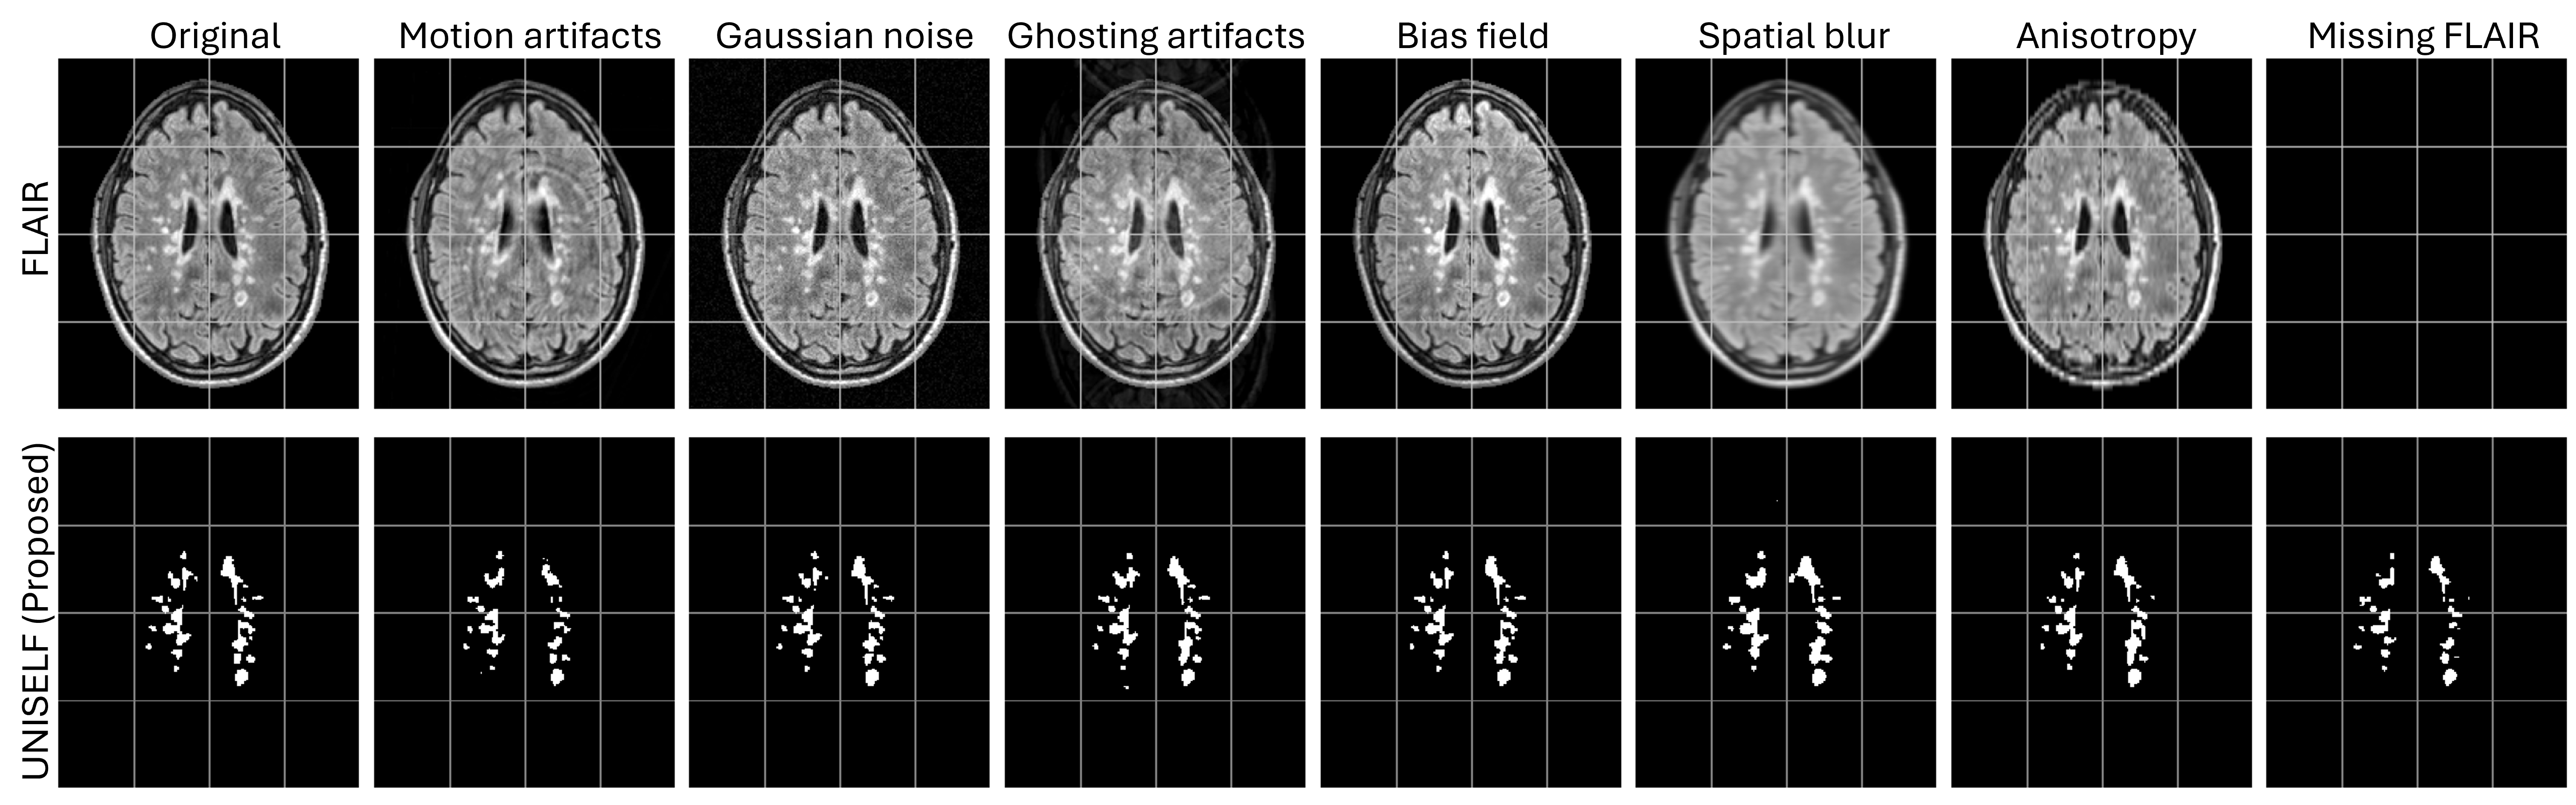

To further validate the generalization performance of trained models to imaging artifacts, FLAIR images in the Test Dataset IV were corrupted with various artifacts, including motion, Gaussian noise, ghosting, bias field, spatial blur, and anisotropy, using the TorchIO data augmentation library [54], as well as missing FLAIR. Examples of corrupted images of one representative subject are shown in Fig. 4.

Figures 5, S2, and S3 show MS lesion masks predicted by different methods on a representative subject from the private test dataset, demonstrating segmentation on the original contrast (Fig. 5), FLAIR with motion artifact (Fig. S2), and input with missing FLAIR (Fig. S3). In Fig. 5, missed lesions were observed in the benchmark methods Tiramisu and CD (contrast dropout). In contrast, the benchmark methods DG (domain generalization) with BN and IN, the benchmark method nnU-Net, and the proposed method UNISELF showed very few missed lesions. In Fig. S2, with motion artifacts added to the FLAIR image, more missed lesions were observed in the benchmark methods Tiramisu, ModDrop++, and CD, but were not observed in DG with BN and IN, nnU-Net, and UNISELF. In Fig. S3, only UNISELF and the benchmark method DG with IN demonstrated robust segmentation performance when dealing with missing FLAIR.

Figure 6 shows boxplots of segmentation scores (Eq. (5)) across Test Datasets II, III, and IV for the original multicontrast inputs and the corresponding inputs without FLAIR. UNISELF achieved noticeable improvements compared to the benchmark methods, especially when the FLAIR contrast was missing. Figure 7 shows boxplots of segmentation scores (Eq. (5)) across Test Dataset IV with various artifacts added to the FLAIR contrast. The benchmark methods DG with IN and BN had already been exposed to such artifacts during training through DG augmentation. Nevertheless, UNISELF outperformed all benchmark methods, including DG with BN and IN.